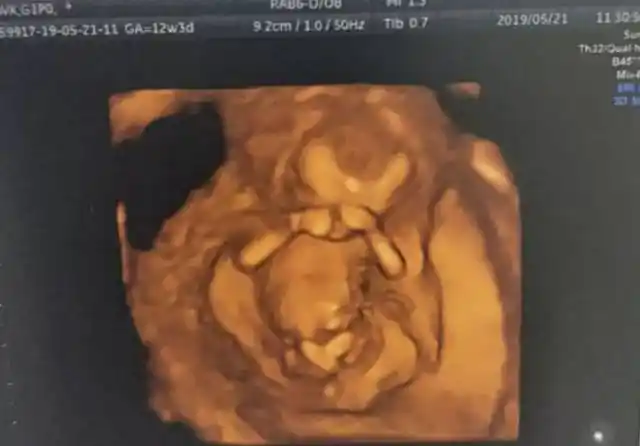

胎儿_颜面_照片